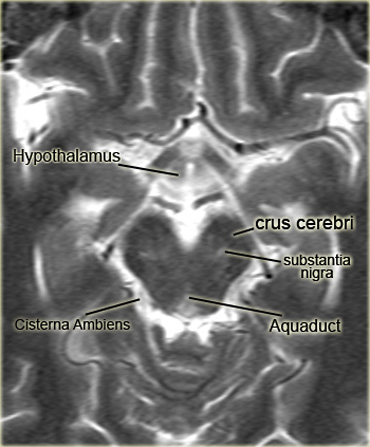

Đoạn M2 là phần nằm trong rãnh Sylvius và đoạn M3 là đoạn vỏ não. - Bể não quanh cuống (Cisterna ambiens)

Còn gọi là bể não xung quanh (ambient cistern), là một bể dịch não tủy thuộc khoang dưới nhện nằm giữa đầu sau thể chai và mặt trên tiểu não.

Đôi khi được định nghĩa bao gồm cả bể tứ giác (quadrigerminal cistern).